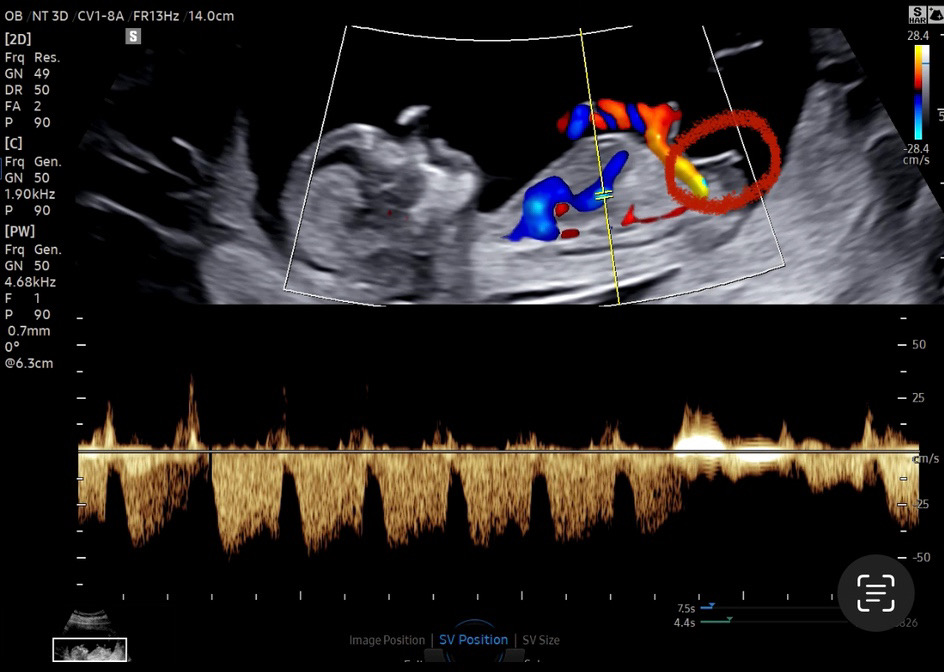

12주 2일 각도법 잘 보시는분!

빌리에서는 다른 각도 사진으로 딸 vs 아들 반반이라 다른 각도 사진 다시 첨부해보아요 😍 어떤거 같나요?!